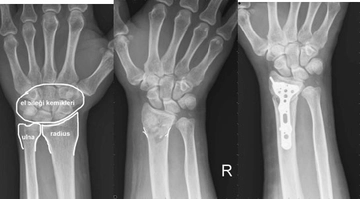

Tanı YöntemleriEl bileği burkulmasının teşhisi genellikle fizik muayene ve görüntüleme yöntemleriyle yapılır. Doktor, aşağıdaki yöntemleri kullanarak tanıyı koyabilir:

Tedavi YöntemleriEl bileği burkulmasının tedavisi, yaralanmanın şiddetine bağlı olarak değişiklik göstermektedir. Tedavi yöntemleri genellikle aşağıdaki gibidir: